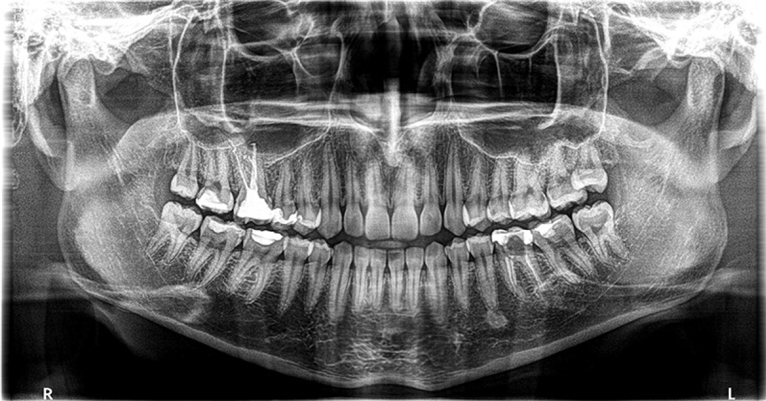

Naš ortopan prikladan je za sve generacije pa tako i za djecu